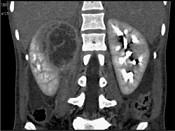

问题 一女性患者,一月前出现尿频、尿急等症状为引起注意,现有高热,阅图后最可能的诊断为 ( )

选项 A.急性肾盂肾炎 B.肾脓肿 C.多囊肾 D.肾结核 E.肾癌

答案 B